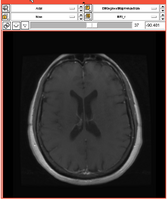

Most clinicians are using the EMSegmenter to segment specific parts of the human body. Those segmentations depend heavily on

the used input data. The signal level in the input data varies with the used image modalities (e.g. MRI, CT, ...) and with each anatomical structure.

The EMSegmenter can take advantage of some knowledge about the signal level of those anatomical structures in the different image modalities.